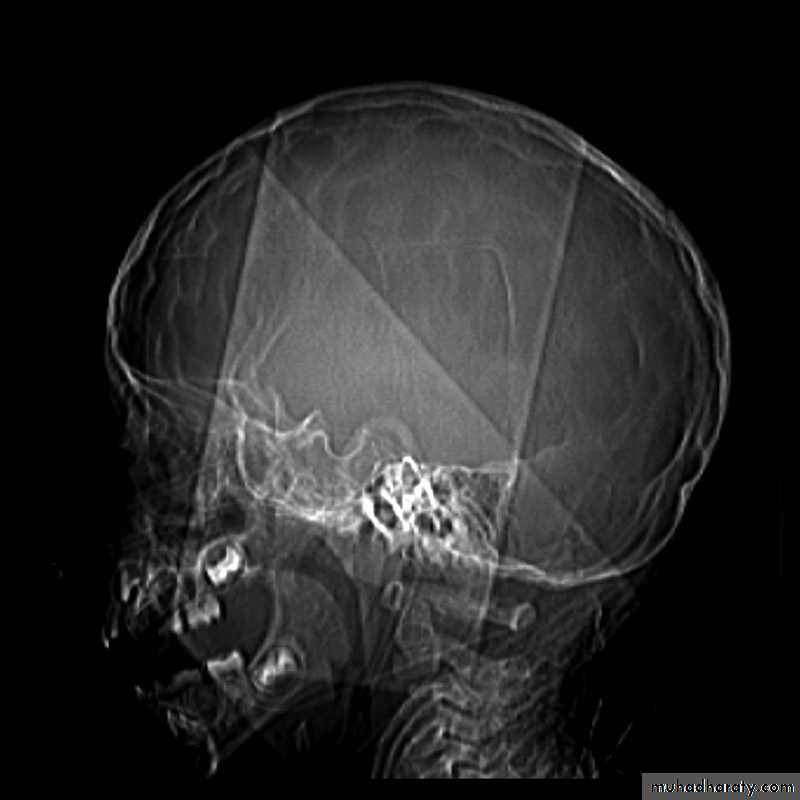

Skull X-ray findings in increased intracranial pressure

• Sutural separation in children.

• ‘Copper-beating’ marking of the cranial vault.

• Thinning of dorsum sellae.

• Erosion of the posterior clinoid process.

Copper-beating’ marking

Neuro surgery